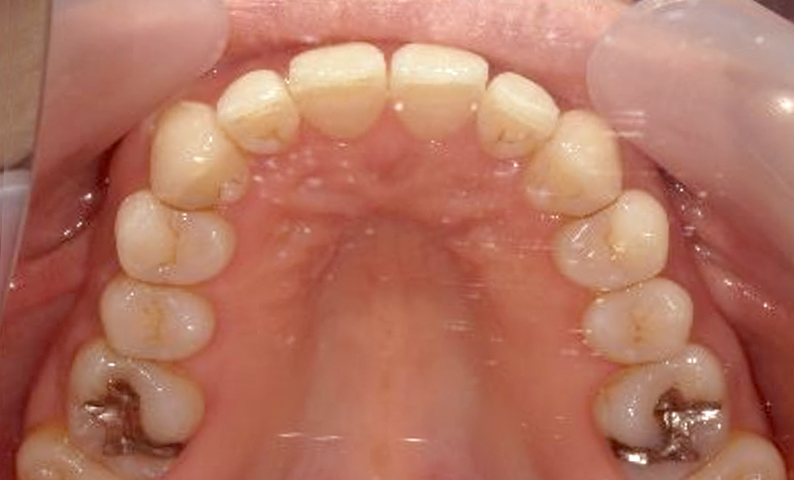

症例_022 上下顎の部分矯正

治療期間:9ヶ月金額:51万円+税女性前歯のガタガタ八重歯

| Before | After |